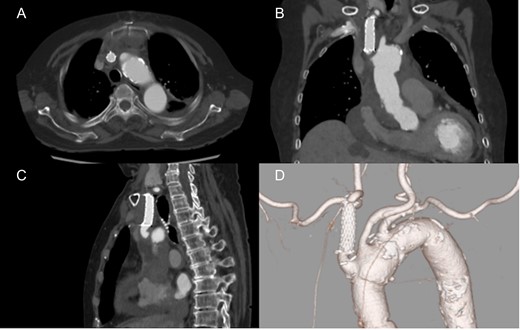

An 86-year-old woman with acute type A aortic dissection was transferred to our institution. Contrast enhanced computed tomography (CT) showed aortic dissection involving the ascending aorta extending to the proximal descending aorta. The true lumen of the brachiocephalic artery was occluded by the false lumen (Fig. 1). No neurological symptoms were present preoperatively. The patient was transferred to the operating room, and underwent central aortic repair with ascending aortic and bicaval cannulations. Cerebral perfusion was monitored with near-infrared spectroscopy (INVOS cerebral oximeter, Somanetics Inc, Troy, USA) and transcutaneous carotid echo. Inside the aorta, the orifice of the brachiocephalic artery was completely occluded by the false lumen. Selective cerebral perfusion (SCP) through the brachiocephalic artery was initiated immediately, however, the SCP flow was not sufficient due to stenotic lesion with low right side regional oxygen saturation (rSO2). Considering low rSO2, it was felt that the lesion should be treated even without preoperative neurological symptoms. The S.M.A.R.T. Vascular Stent System (Cordis Corp, Fremont, CA, USA) (12 mm × 40 mm) was inserted and deployed inside the brachiocephalic artery. After SCP cannula was inserted through the stent, right side rSO2 increased similar to the left side. Finally, ascending aortic replacement by using 26 mm J-Graft (Japan Lifeline Co., Ltd., Tokyo, Japan) was performed. Postoperative course was uneventful without any neurological event. Postoperative CT scan showed good stent patency and no residual dissection in the brachiocephalic artery (Fig. 2).

Postoperative computed tomography showing patent carotid stent and no residual dissection. Axial (A), coronal (B) and sagittal view (C). 3D computed tomography angiography (D).